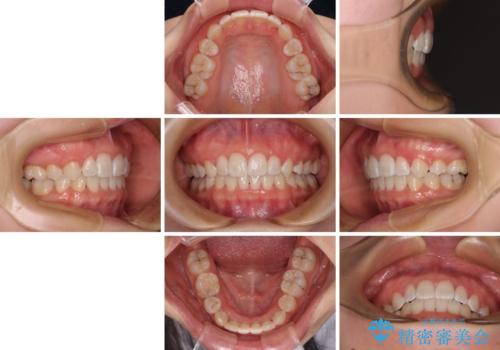

口元の突出感がない分、奥歯を前方に移動させる必要がありましたが、予定の2年間で無事に治療を終えることができました。

口元の突出感はあまりなかったものの、デコボコを非抜歯で改善すると出っ歯になる可能性があるため、上下左右の第一小臼歯4本を抜歯し、ワイヤー装置にて矯正治療を行うこととしました。